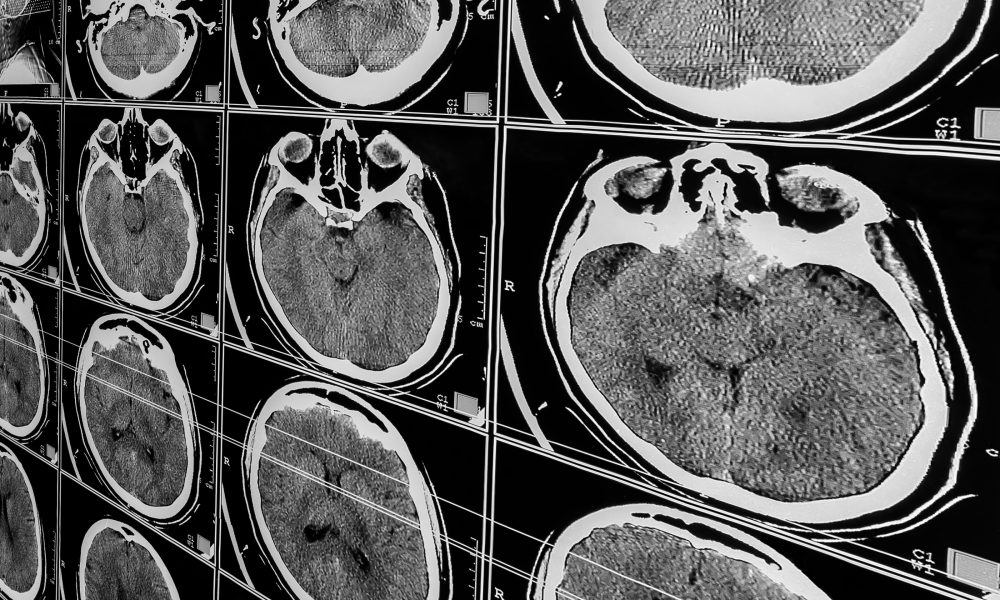

All participants underwent a PET scan of the head to evaluate and quantify amyloid changes. Analysis software was used to segment six brain regions that are usually associated with Alzheimer’s disease and TBI.

Abnormal amyloid accumulation was seen in six of the nine participants who were exposed to explosions. Three of the participants had one region of the brain with increased amyloid accumulation, two participants had two regions, and one participant had three regions with abnormal accumulation.

None of the healthy control participants showed any abnormal amyloid accumulation.